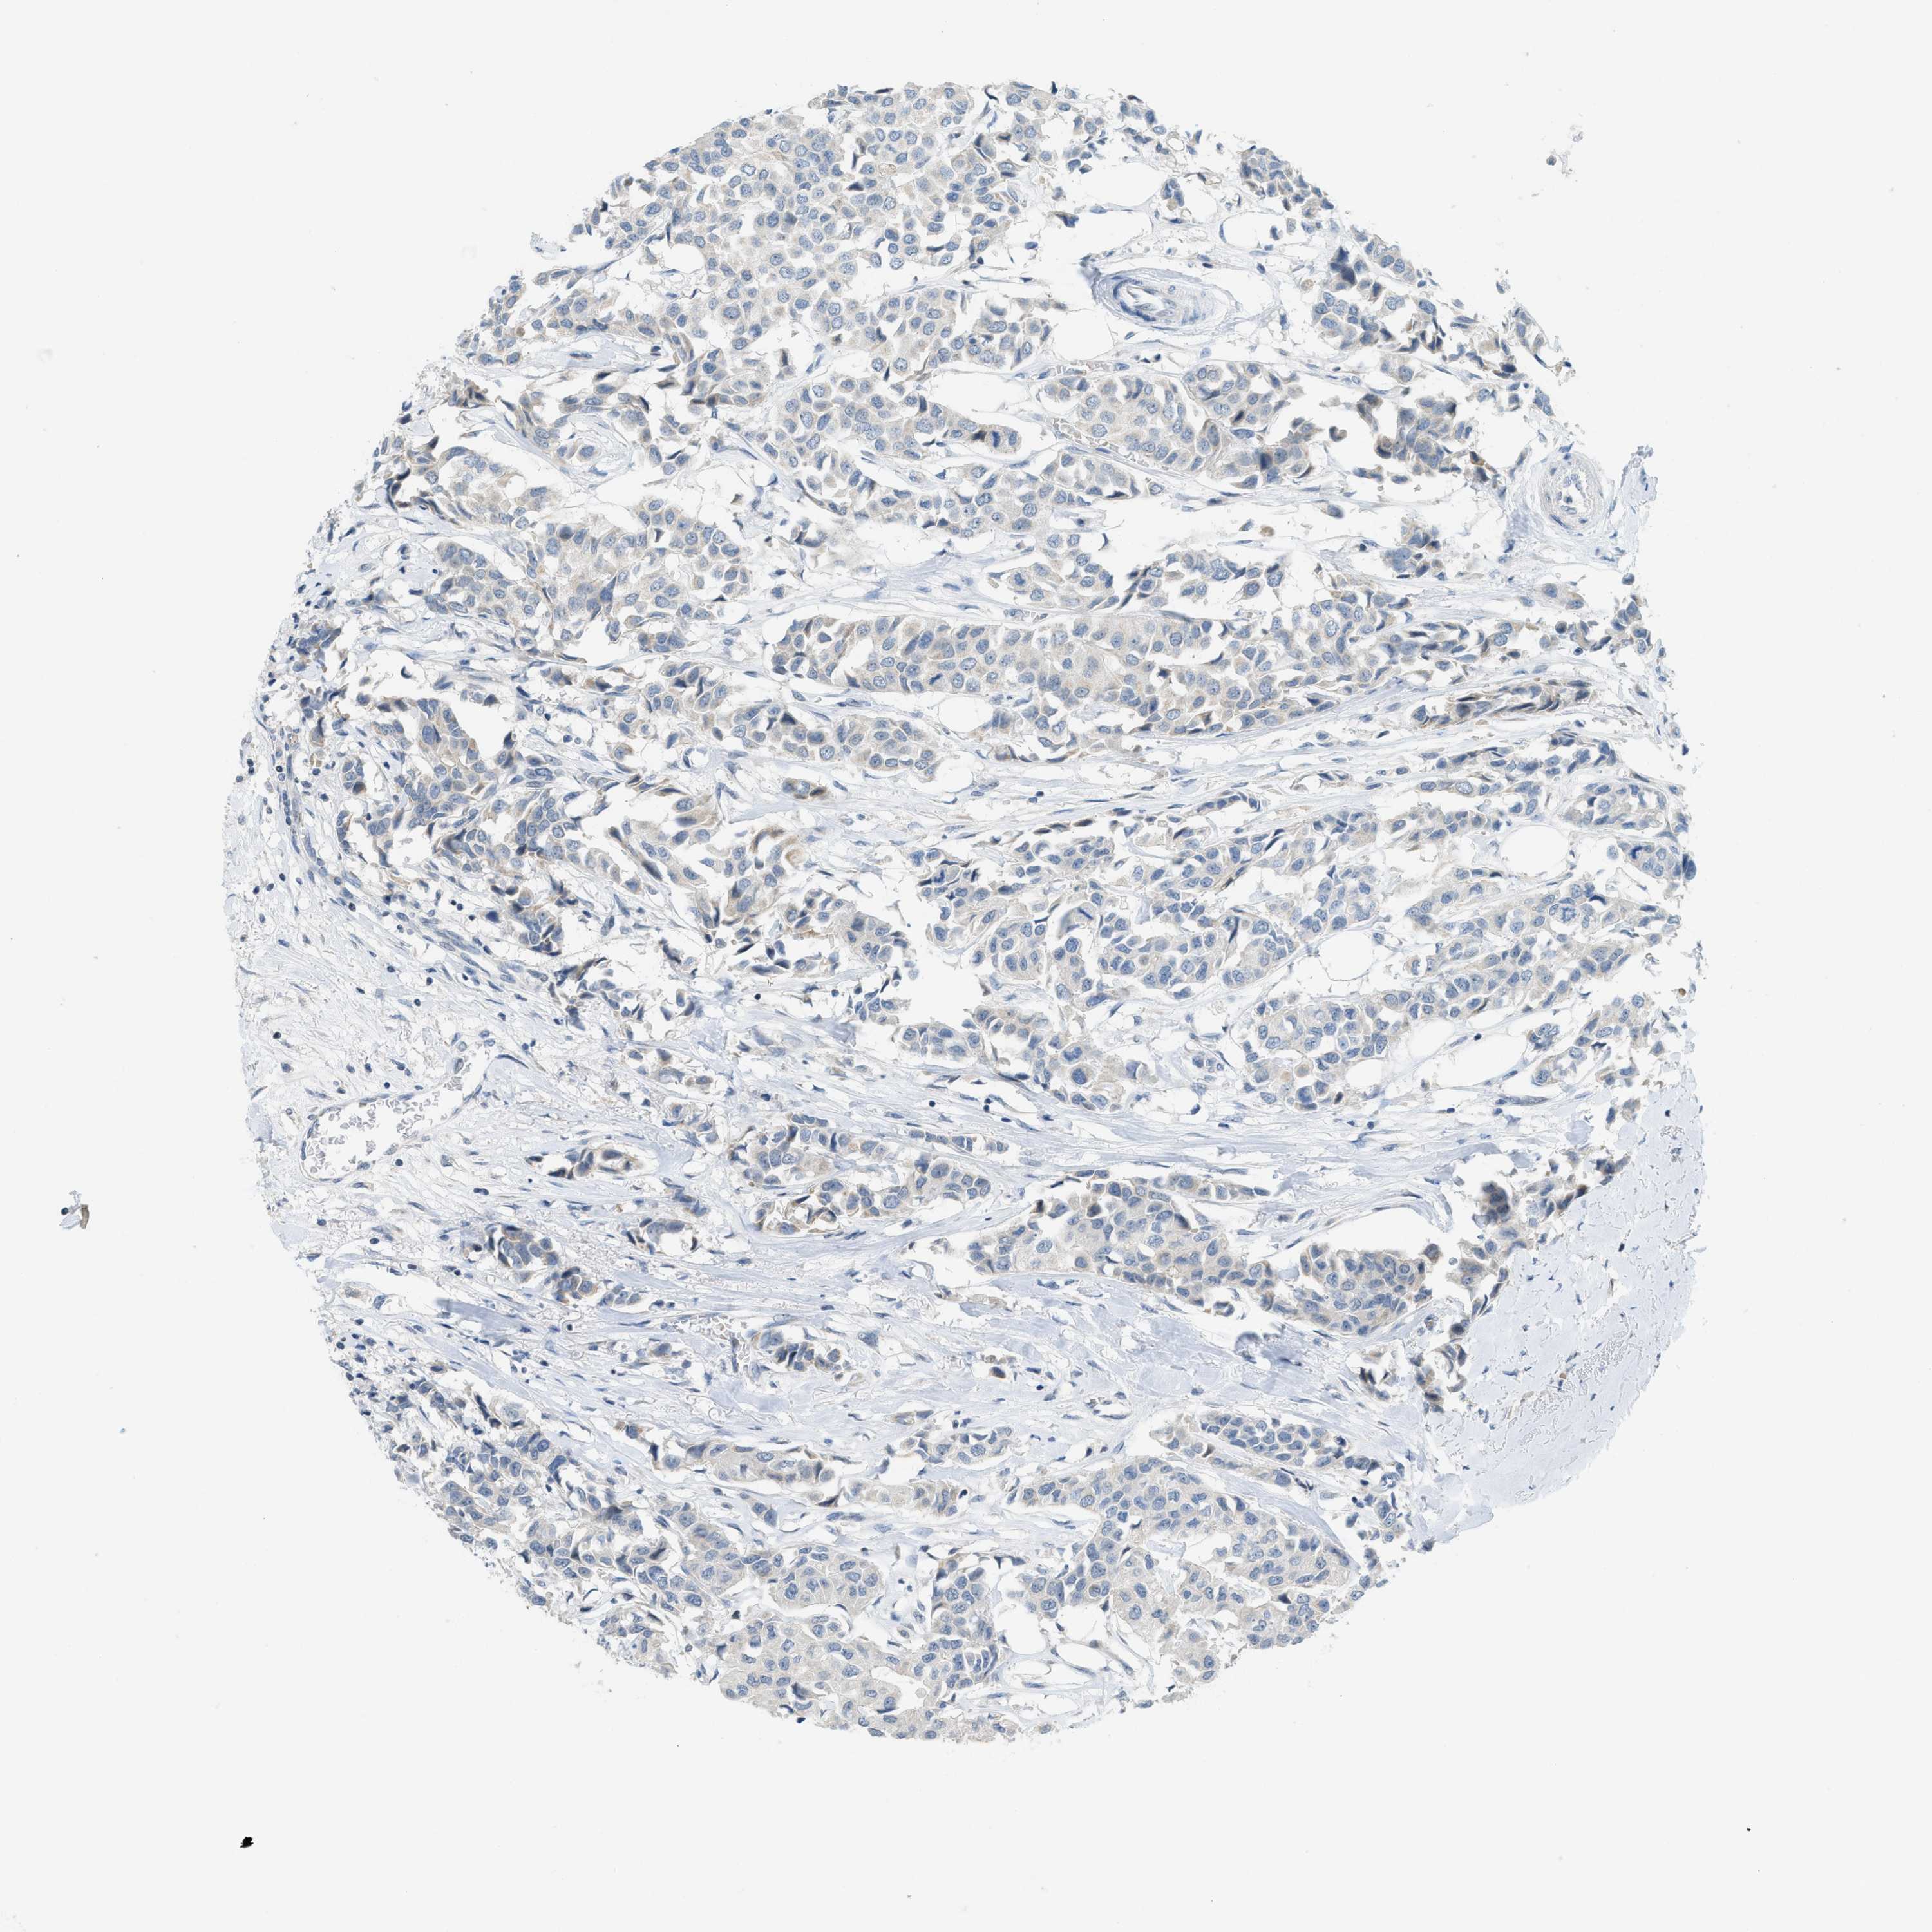

BRCA TCGA BRCA VALIDATION PROTEIN EXPRESSION

ANTIBODIES

AND

VALIDATION